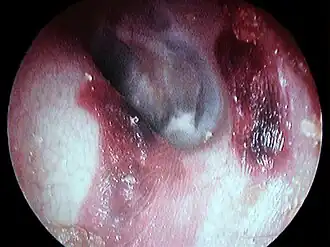

Bouchon de cérumen complet dans le conduit auditif

Hématome du conduit auditif externe gauche post coton tige